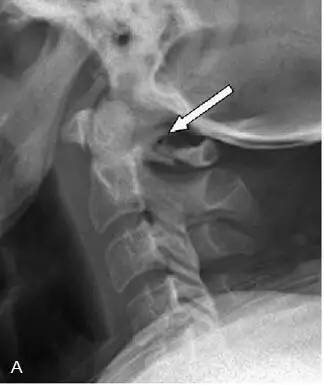

【影像学表现】

CR: C1侧块相对C2侧块外侧移位约5 – 6 mm,符合Jefferson骨折。椎体周围软组织明显肿胀。MR: 椎体周围间隙可见血肿。覆膜完整。寰枕前韧带断裂。寰枢前韧带完整。左侧横韧带从C1侧块的内侧分离,CT对应在C1侧块内侧见小撕脱骨折。翼状韧带完整。寰枕后韧带完整。前纵韧带和后纵韧带完整。黄韧带完整。

Jefferson骨折(Jefferson fracture)是前后弓均累及的C1环粉碎性骨折。Jefferson骨折为头顶受打击并轴向载荷的结果,力从颅骨经枕骨髁传递到颈椎,C1侧块在枕骨髁和C2上关节面之间被压缩,基于侧块的形状产生向心力而导致C1爆裂骨折。齿状突开口位或冠状位重建CT图像应仔细观察双侧C1和C2关节侧块间有无偏移。虽然C1侧块相对C2上关节面侧方移位提示存在骨折,但在X线片上有时难以发现骨折线。MR可显示相应的韧带损伤。

警告:C1异常时单侧或双侧寰枢椎侧方偏移可达2 mm,而Jefferson骨折通常偏移3 mm或以上。